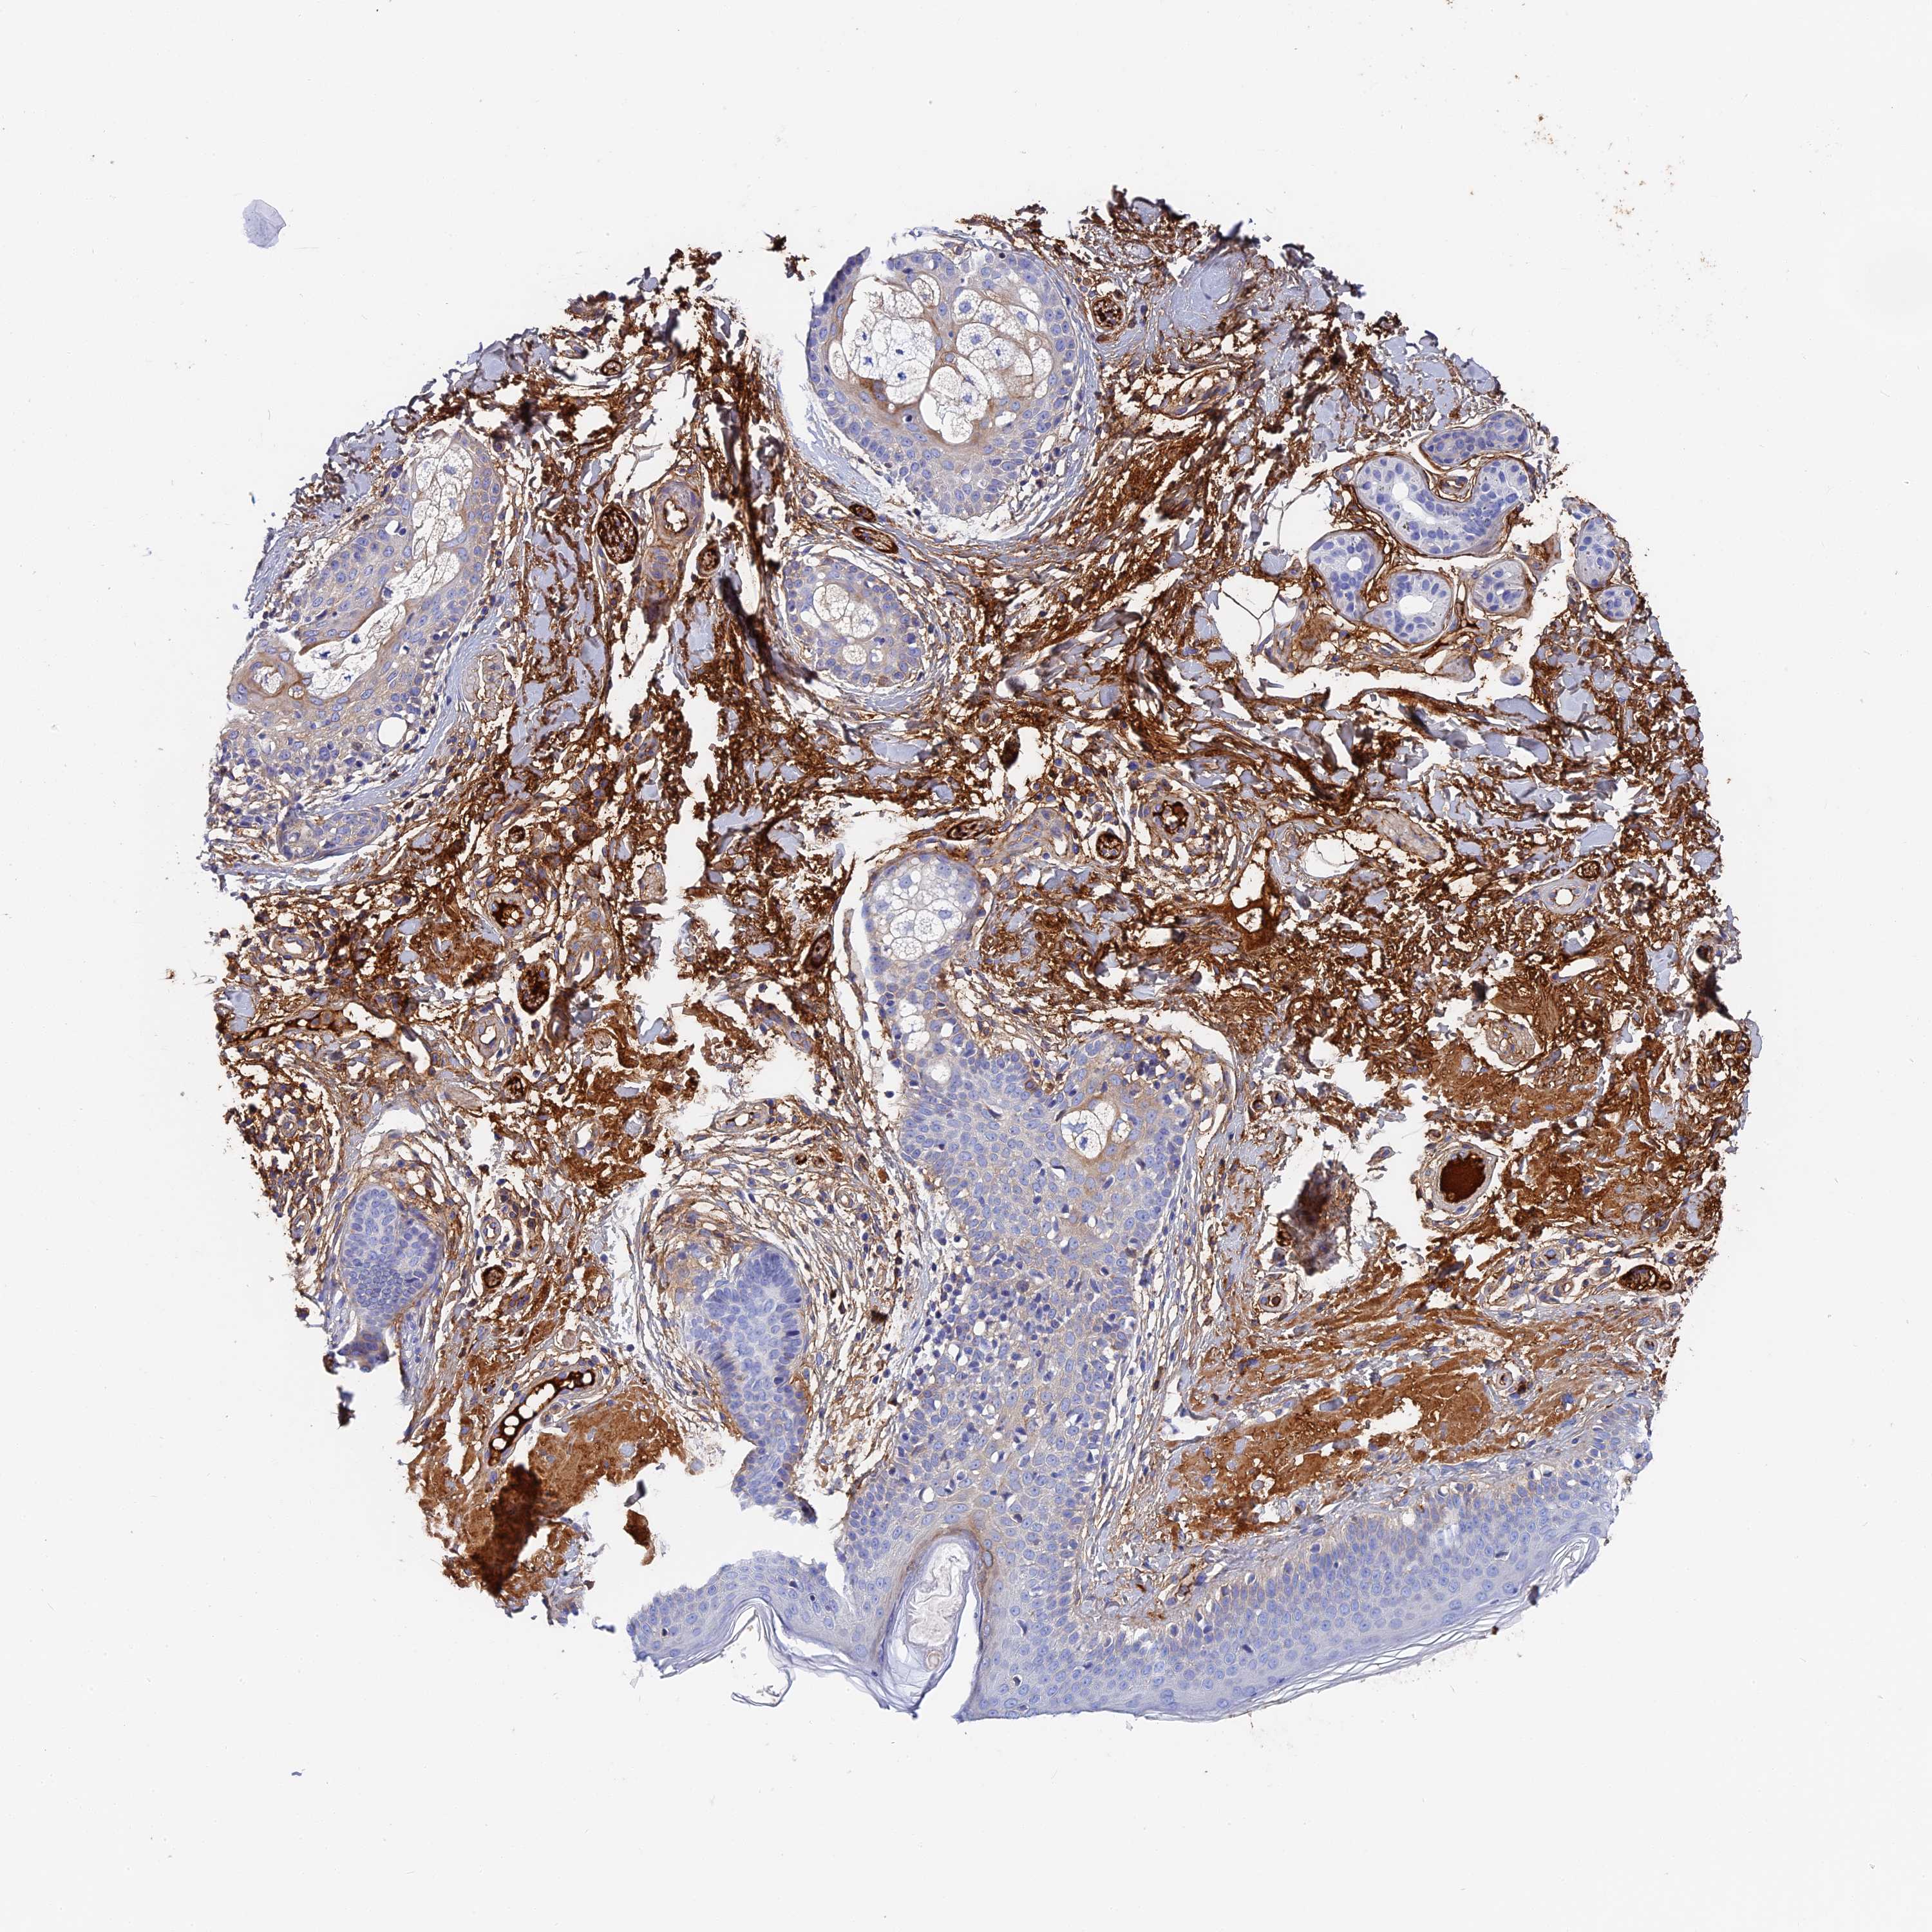

SKIN CANCER - Protein expressioni

A mouse-over function shows sample information and annotation data. Click on an image to view it in a full screen mode. Samples can be filtered based on level of antibody staining by selecting one or several of the following categories: high, medium, low and not detected. The assay and annotation is described here.

Antibody stainingi

Antibody staining in the annotated cell types in the current human tissue is reported as not detected, low, medium, or high, based on conventional immunohistochemistry profiling in selected tissues. This score is based on the combination of the staining intensity and fraction of stained cells.

Each image is clickable and will lead to virtual microscopy that enables deeper exploration of all samples and also displays staining intensity scores, fraction scores and subcellular localization as well as patient and tissue information for each sample.

Antibody HPA041639

Antibody HPA042049

Squamous cell carcinoma, NOS